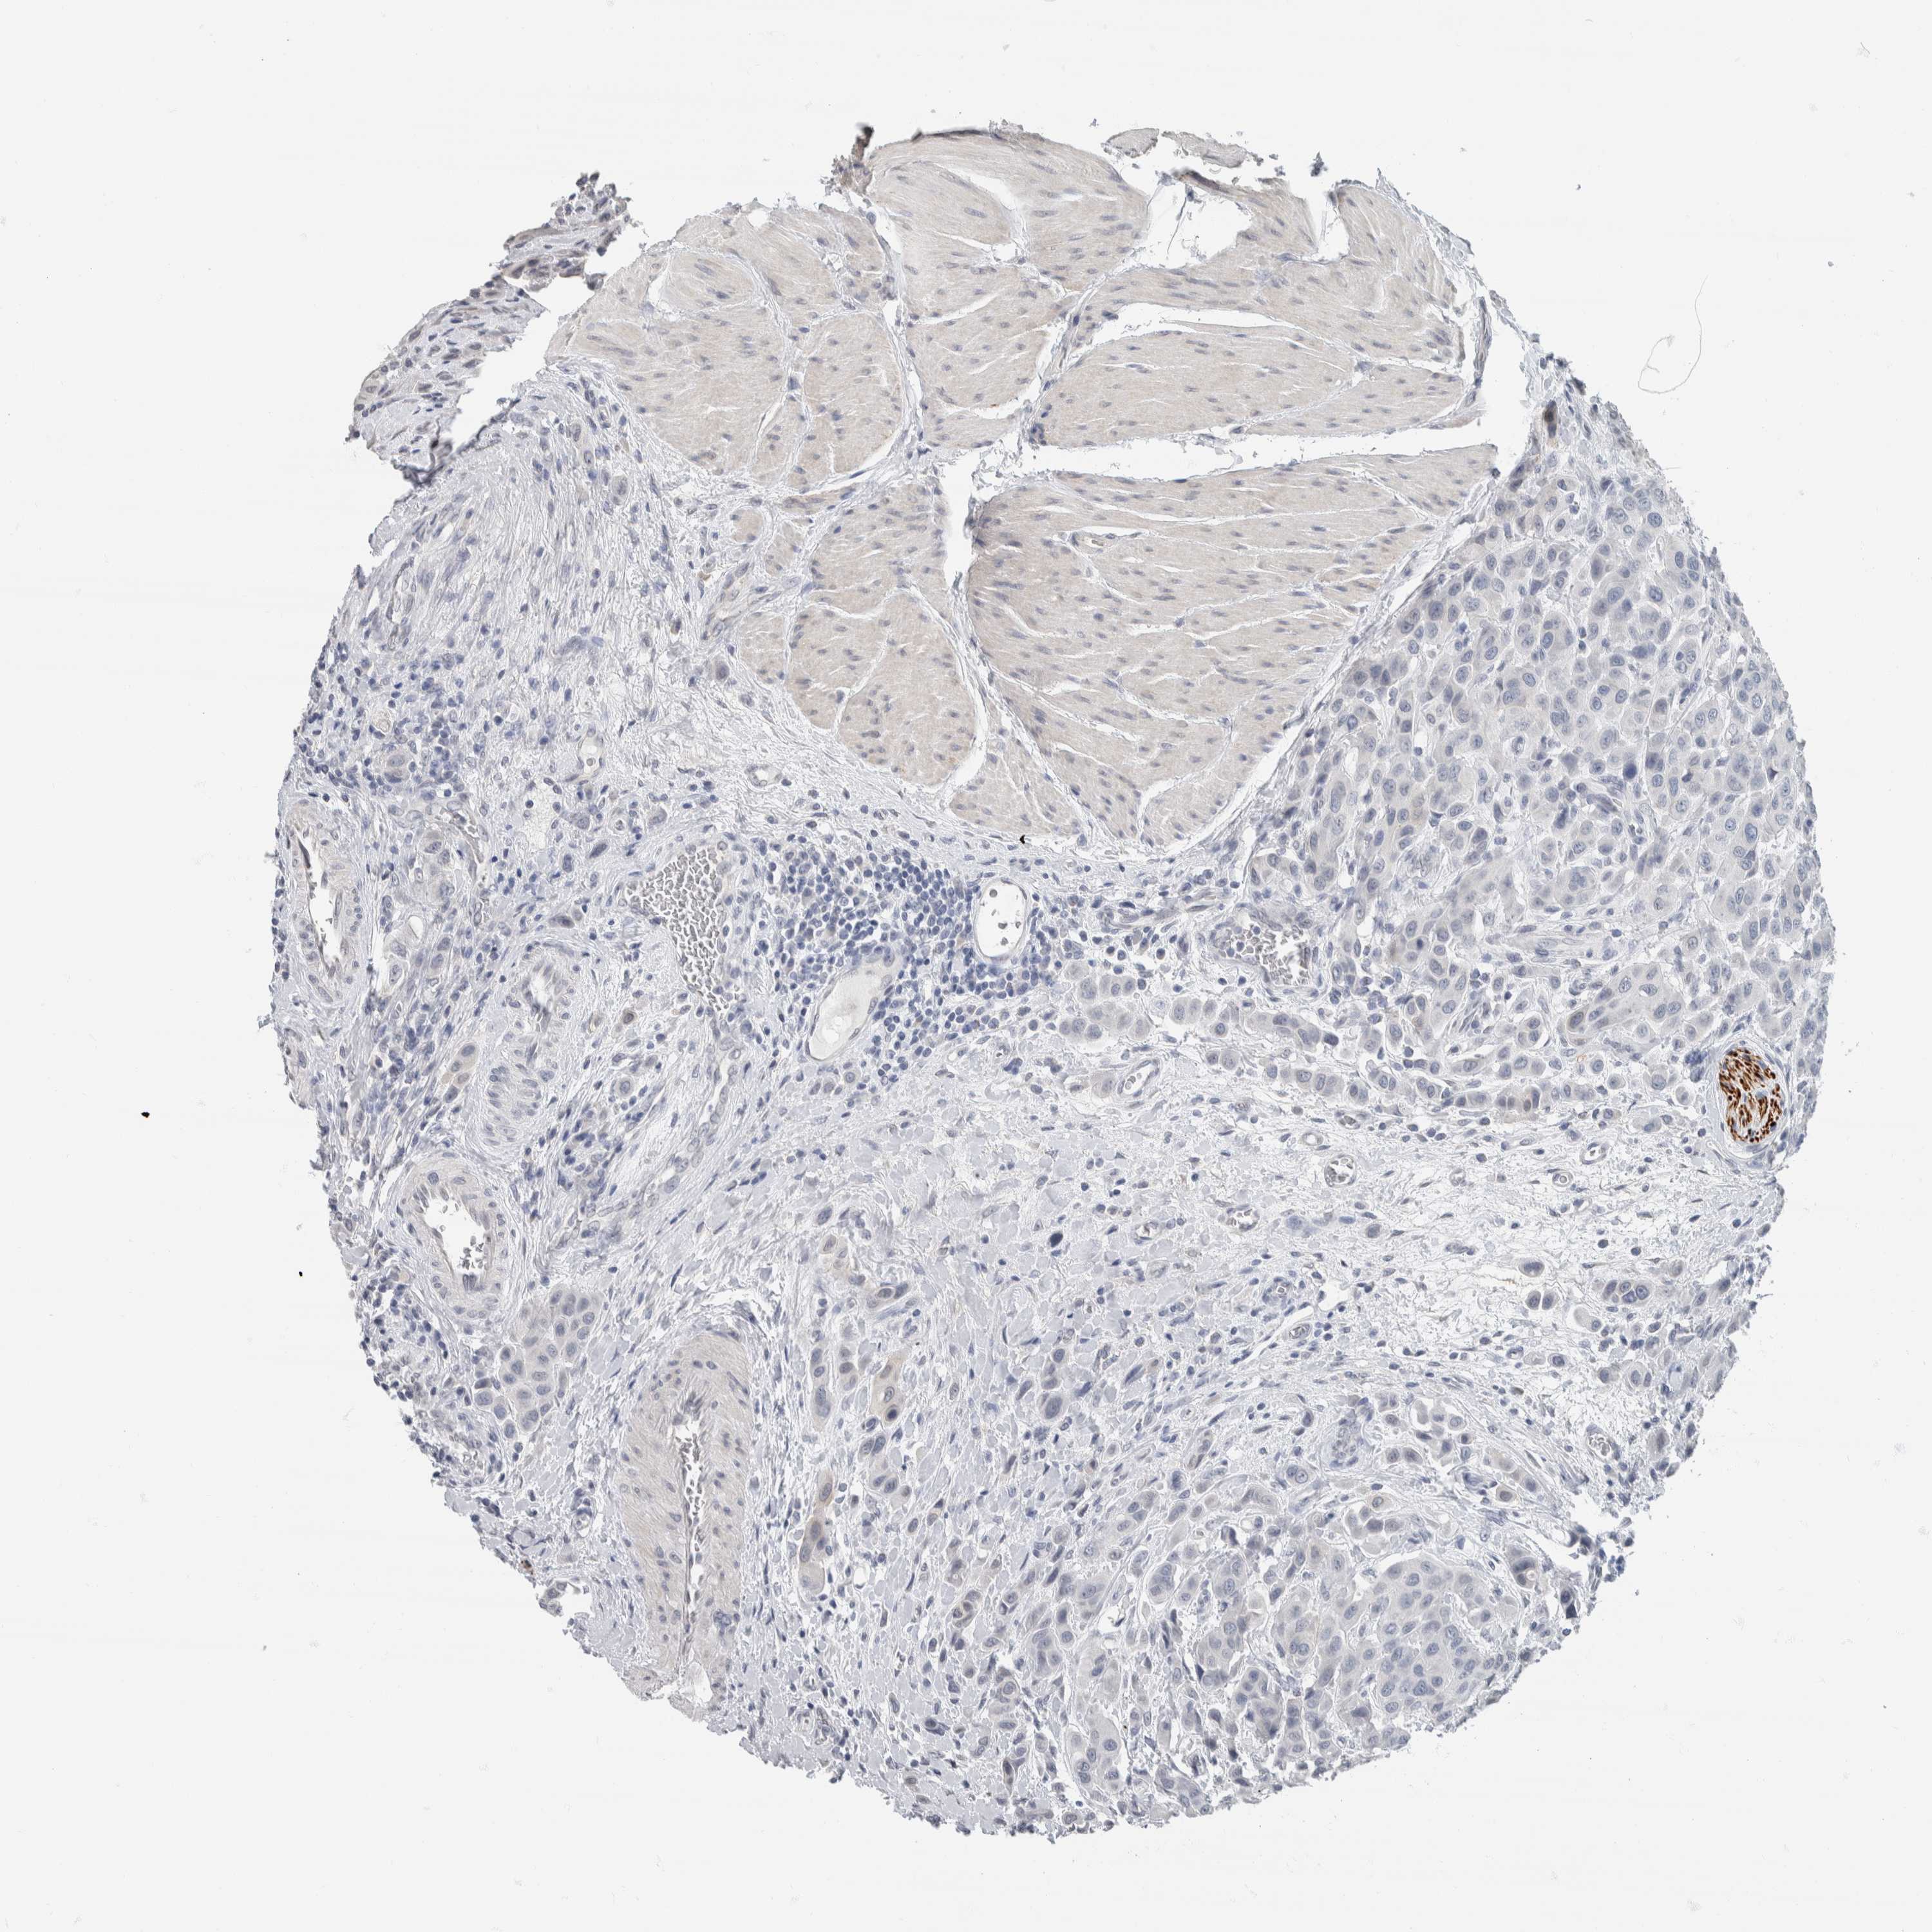

UROTHELIAL CANCER - Protein expressioni

A mouse-over function shows sample information and annotation data. Click on an image to view it in a full screen mode. Samples can be filtered based on level of antibody staining by selecting one or several of the following categories: high, medium, low and not detected. The assay and annotation is described here.

Note that samples used for immunohistochemistry by the Human Protein Atlas do not correspond to samples in the TCGA dataset.

Antibody stainingi

Antibody staining in the annotated cell types in the current human tissue is reported as not detected, low, medium, or high, based on conventional immunohistochemistry profiling in selected tissues. This score is based on the combination of the staining intensity and fraction of stained cells.

Each image is clickable and will lead to virtual microscopy that enables deeper exploration of all samples and also displays staining intensity scores, fraction scores and subcellular localization as well as patient and tissue information for each sample.

Antibody HPA022845

Antibody HPA023138

Antibody CAB010900

Antibody CAB012976

Staining

High

Medium

Low

Not detected

Intensity

Strong

Moderate

Weak

Negative

Quantity

>75%

75%-25%

<25%

None

Location

Nuclear

Cytoplasmic/membranous

Cytoplasmic/membranous,nuclear

Urothelial carcinoma, Low grade

Urothelial carcinoma, High grade